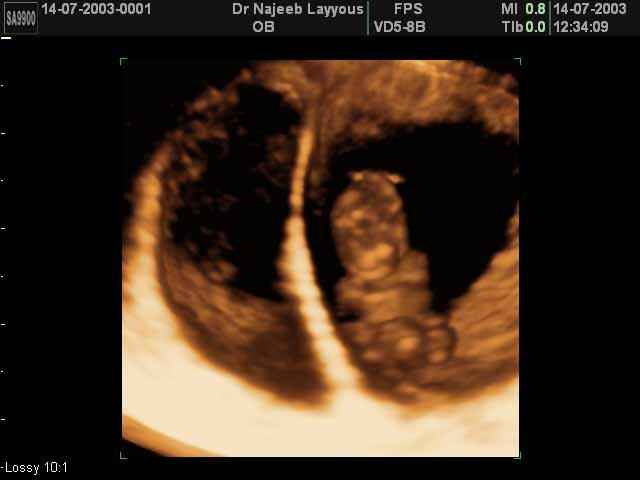

- لقطات فيديو للجنين بجهاز الموجات فوق صوتية رباعي الأبعاد

- صور للجنين في المراحل الأولى من الحمل

- صور لتصرفات الجنين داخل الرحم